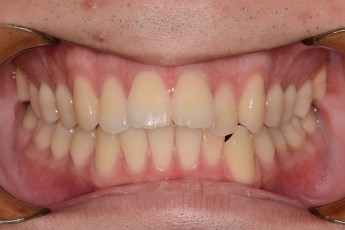

BEFORE & AFTER

- 덧니교정

- 돌출입교정